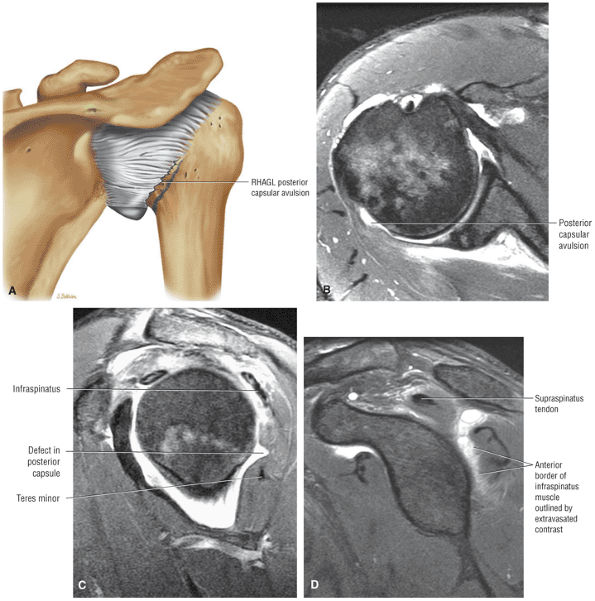

capsule, posterior dislocation does not occur even with division of the posterior capsule. The posterior capsule is torn in reverse HAGL lesions.73